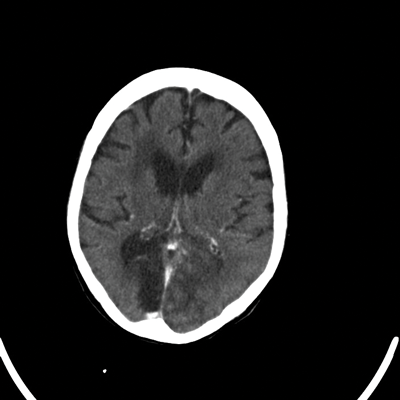

Her physical and neurological examinations were normal. Routine blood and urine tests were normal. She had an urgent CT scan which confirmed bilateral occipital infarction with hemorrhagic conversion. Aspirin was started by the medical team and she was referred to the ophthalmologist for reducing visual acuity.

Figure 1: CT scan report: On the unenhanced scan showing large area of mixed attenuation in the left occipital lobe. Post contrast there are some gyriform enhancement features likely to indicate acute hemorrhagic infarct. There is a well defined area of low attenuation in the right occipital lobe consistent with the established infarct. There is a further area of low attenuation in the right frontoparietal region likely due to an ischaemic aetiology.